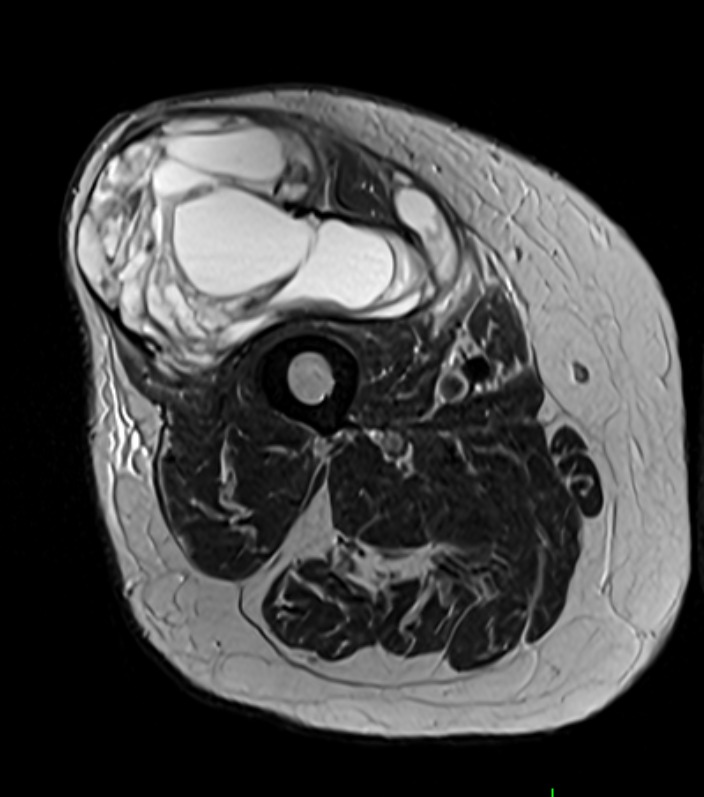

Muscle Cancer